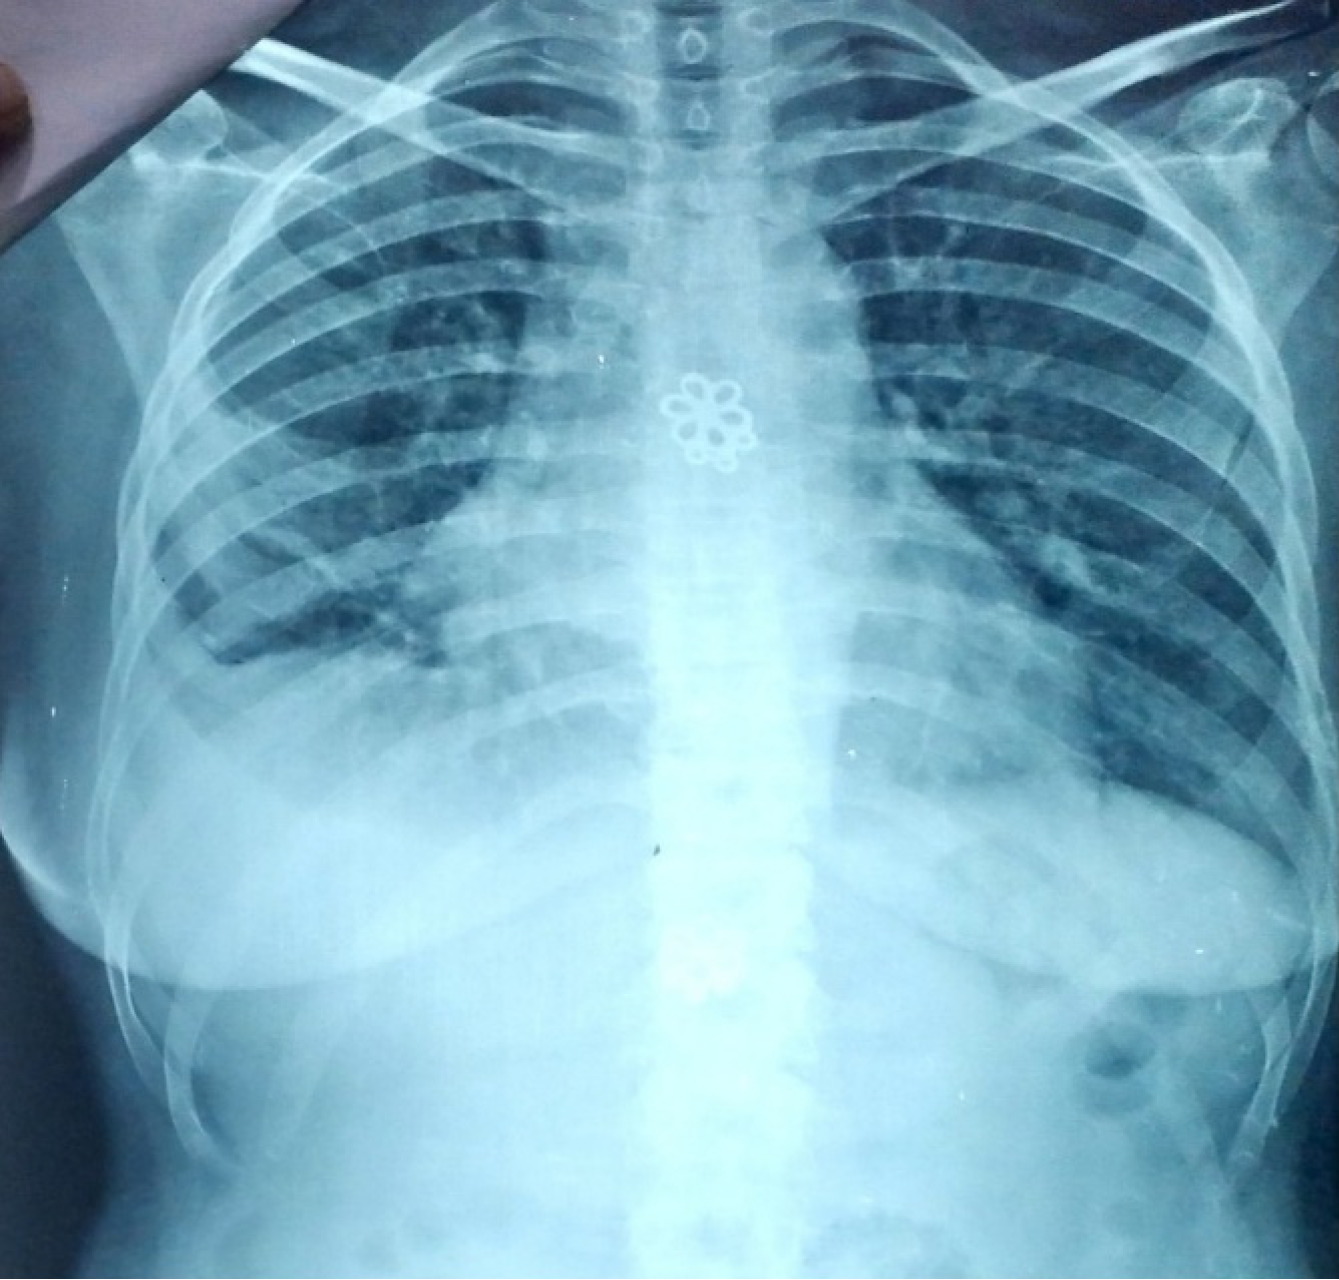

Figure 1

Chest X-ray anteroposterior view.